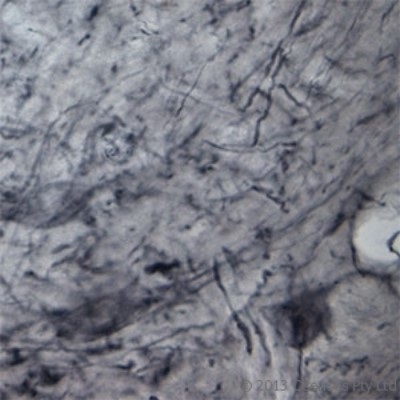

- Immunohistochemistry: P2X6/P2RX6 Antibody [NBP1-30565] - IHC on rat spinal cord (free floating section) using Rabbit antibody to extracellular domain of P2X6 (P2RX6, P2X purinoceptor 6, ATP receptor, P2RXL1): whole serum at 1 : 300 dilution incubated overnight at room temperature (21C) and developed with DAB/Ni.